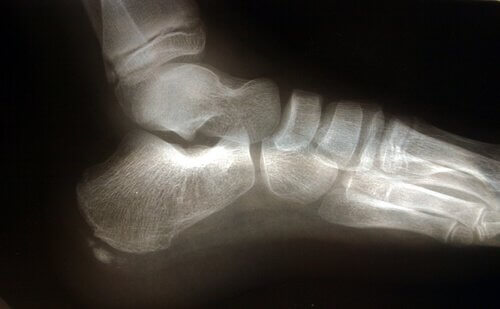

تشريح القدم

تلعب عدة هياكل تشريحية مختلفة دورًا في الضغط المفرط على الرباط الأخمصي.

وتر أخيل هو رباط يصل بين عضلة الساق، والمعروفة بالربلة، والعضلية النعلية، وعظم الكعب.

انقباض وتر أخيل يضع ضغطًا زائدًا على عظم الكعب، مما يؤدي بدوره إلى زيادة الضغط على اللفافة الأخمصية.

فيما يتعلق بالهياكل التشريحية، يجب أخذ عامل آخر في الاعتبار، ألا وهو ضربة القدم، أو كيفية لمس القدم للأرض أثناء الحركة.

القدم المسطحة التي تميل إلى الكَبّ تسبب تمدد اللفافة الأخمصية أكثر، وهو ما يزيد خطر الإصابة بالتمزقات والألم.

التهاب اللفافة الأخمصية ترتبط عادةً بظهور نتوء عظمي، ولكنه ليس عامل مُحدّد.